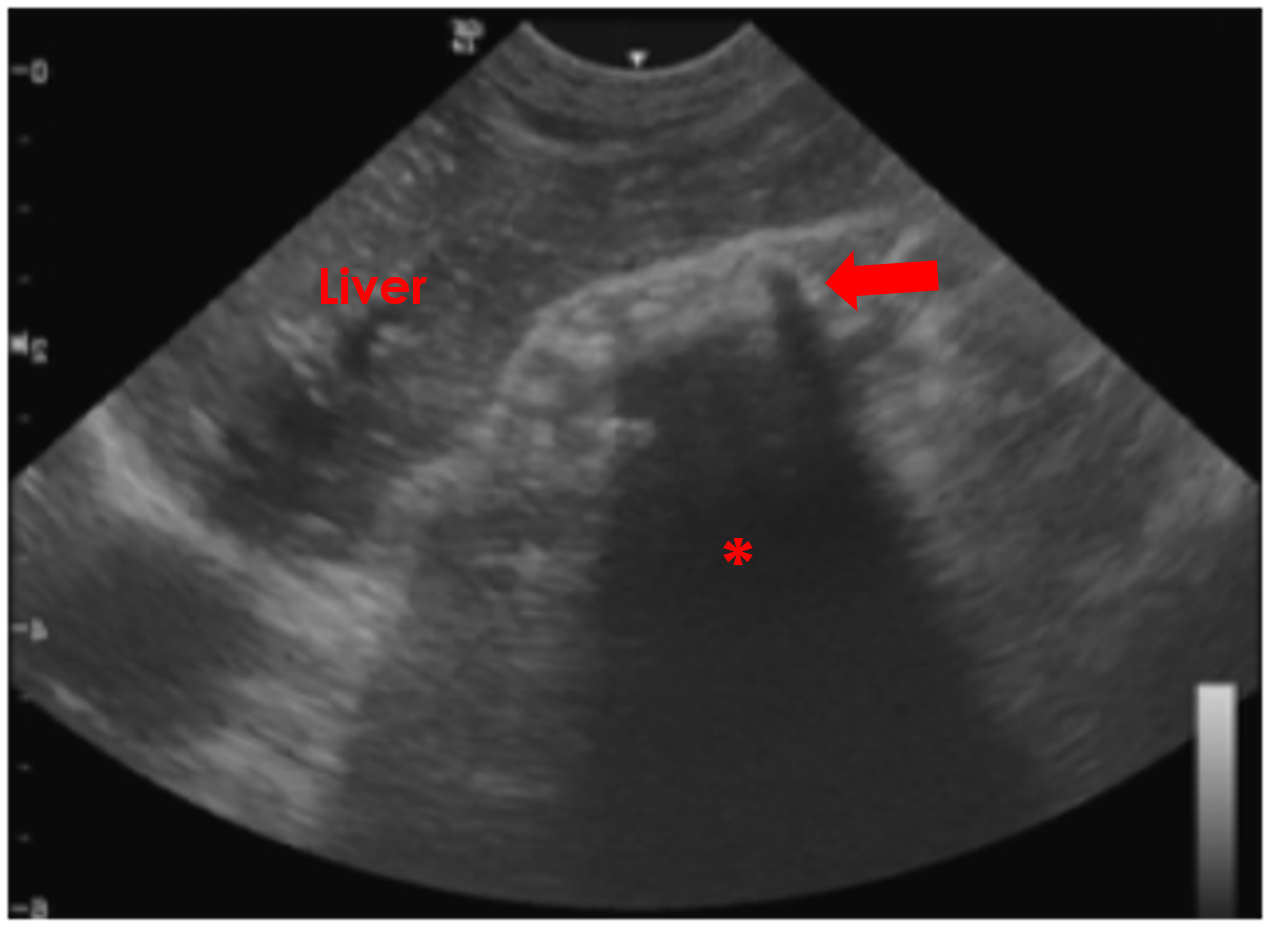

Figure 12. Gastric Foreign Body – In this sagittal oblique image of the cranial abdomen of a dog, a plastic foreign body in present within the gastric lumen (arrow). The dense plastic of the foreign material is preventing the ultrasound waves penetrating deeper into the patient and creating an acoustic shadow artefact (*).